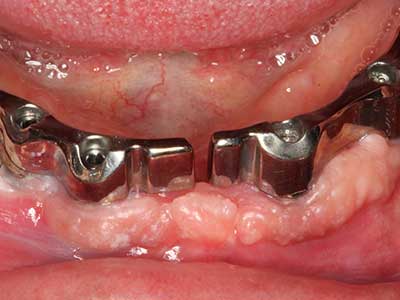

Piezo surgery has additional advantages when harvesting bone blocks. In addition to the high precision with osteotomy described above, the use of the thin saw tips specifically minimizes loss of material. Greater loss of material during harvesting can be expected with the thicker instrument tips, particularly when using Lindemann drills (Lakshmiganthan, Gokulanathan et al. 2012). The basal separation, which is necessary particularly for retromolar block transplants, is simplified by specially designed rectangular saws, with the result that piezo surgery is viewed as a precise, simple and safe procedure for harvesting retromolar bone blocks (Happe 2007) (Fig. 1-12).

Indication: Bone splitting